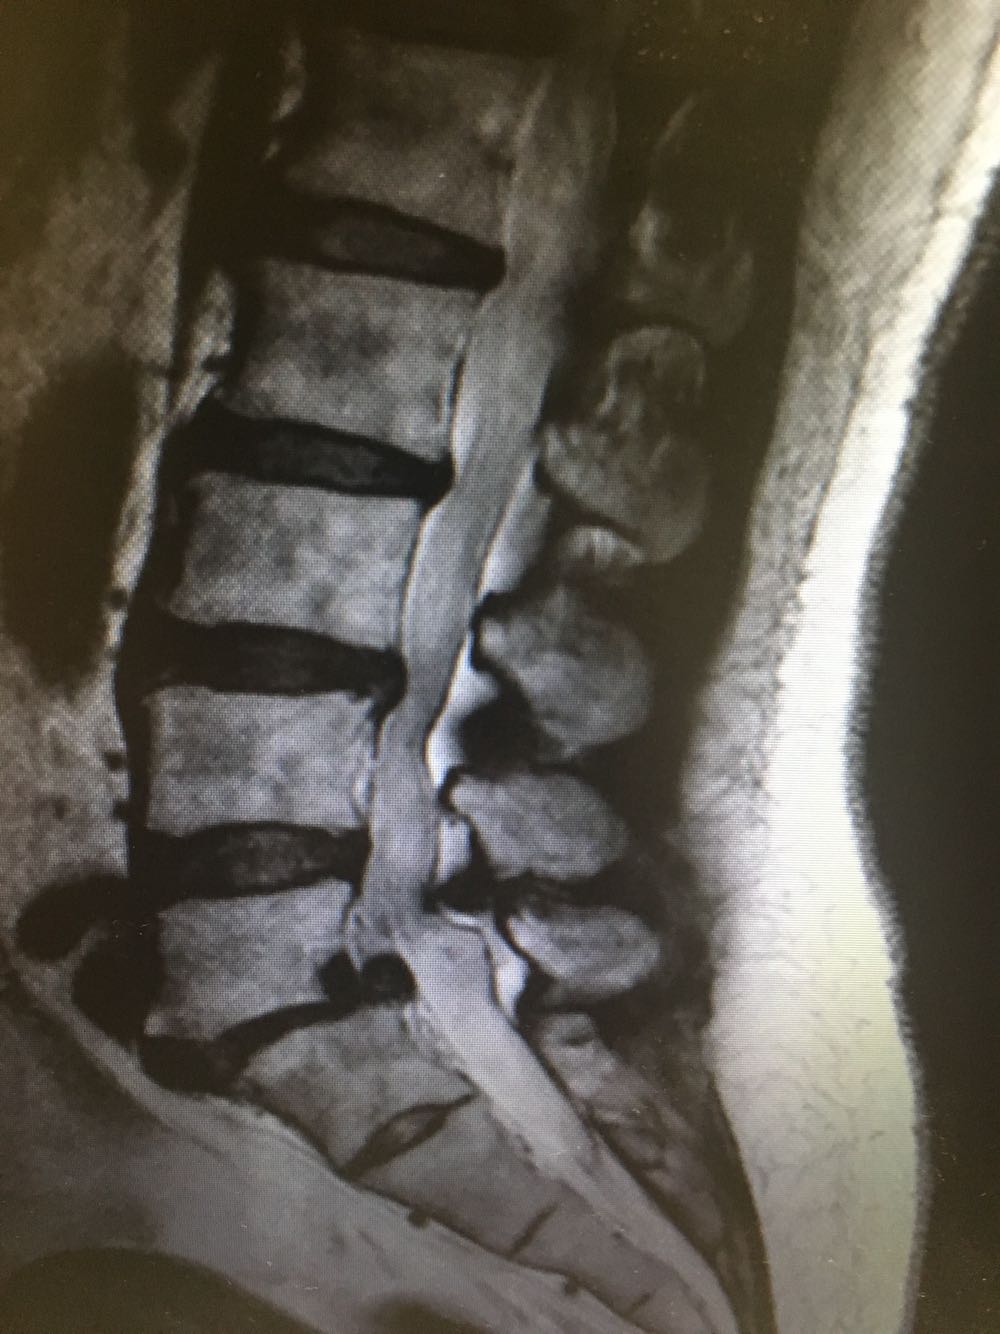

患者,女性,60岁 主诉:腰痛伴下肢疼痛2年 现病史:患者于2年前无明显诱因下出现腰痛伴左侧下肢疼痛,休息后缓解,未予重视,半年前出现双下肢外侧疼痛,酸胀伴跛行,休息后稍缓解,病程中否认头晕头痛、恶心呕吐等不适,遂至我院门诊就诊,查腰椎X片示:L5椎体向前轻度滑脱,伴退行性变,椎间隙变窄,现为进一步诊治收治入院,发病以来,神清,精神可,胃纳夜眠可,二便无殊,体重无明显变化。

查体:脊柱无侧弯畸形,下肢肌力肌张力正常,下肢反射均正常。 辅检:腰椎MRI